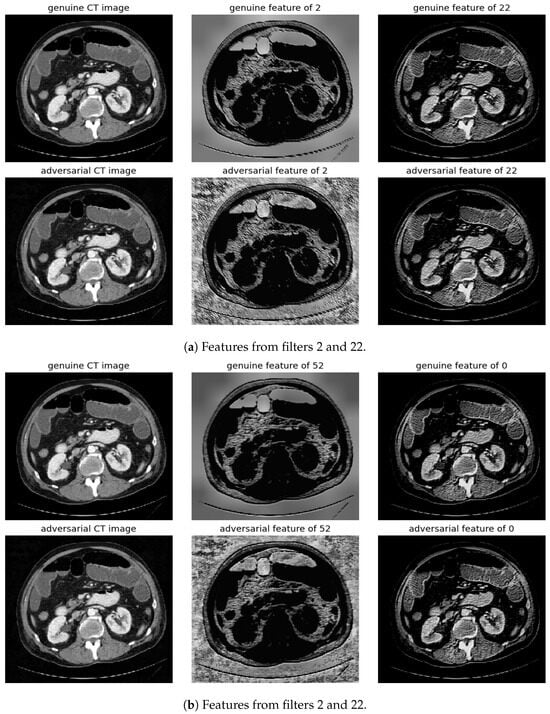

Randomly selected genuine CT samples, alongside their adversarial versions, are displayed in Figure 9, Figure 10 and Figure 11. The adversarial samples were generated using FGSM, BIM, and SMIA attack methods, each with an epsilon of 0.01. While BIM and SMIA used 5 iterations, FGSM did not. These samples represent the most challenging scenarios for human visual detection. Despite the modest epsilon value, as indicated in Table 3, the adversarial attacks have a subtle but pronounced effect. Such slight modifications can lead to major diagnostic inaccuracies potentially impacting patient care.

Figure 10.

Visualization under BIM Attack: Comparisons of features from the first layer between genuine and adversarial samples for the most sensitive (filters 2 and 52) and least sensitive (filters 22 and 0) filters.

To address this, histogram equalization as feature post-processing is applied. The visual representations underscore that while genuine and adversarial samples might appear similar to the naked eye, post-processing brings forth distinct feature differences when employing the most sensitive filters from 2 and 52. Perturbations, especially noticeable in the background of the adversarial samples, are frequently highlighted by these filters. Conversely, features processed with filters from 22 and 0, deemed less sensitive in prior analyses, fail to offer a stark visual contrast.